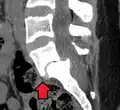

RM de anterolistesis L5-S1 -

(A) Vista sagital de CT de un deslizamiento de bajo grado.

(B) Intervención preoperatoria de radiografía lateral.

(C) Tratado quirúrgicamente con descompresión L5 – S1, fusión instrumentada y colocación de un injerto intersomático entre L5 y S1.